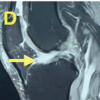

Magnetic resonance imaging (MRI) (Fig. 3) showed irregularity, sclerosis, fat deposit, and slight hypertrophy at the pubic symphysis, consistent with chronic pubic osteitis, as well as bone edema at both pubic bones in accordance to an acute inflammatory component. Both femoral heads showed no alterations. Physical therapy resulted ineffective. Ultrasound-guided joint puncture showed neither drainable abscesses nor liquid for culture. An ultrasound-guided infiltration of local anesthetic and corticosteroid was performed, showing some improvement at rest within the 1st 48 h but the pain persisted with movement. After 1 year and a half with pain, she was still using opioids daily. Considering non-surgical management non-effective, surgery was proposed. First, rekindling of symphysis pubis was performed and anterior iliac crest graft was harvested. Through an anterior surgical approach an arthrodesis with double plate was performed. Dissection of the cartilage was observed. One plate was placed superior and the other was placed anterior with autologous bone graft. Symphyseal fixation was performed without surgical complications. Intraoperative samples cultures were negative. One month after surgery, she had neither symphyseal pain nor sacroiliac pain. Walking was permitted assisted by a walker, but single leg stance was not allowed.